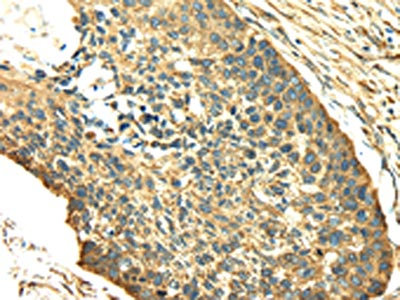

The image on the left is immunohistochemistry of paraffin-embedded Human esophagus cancer tissue using CSB-PA279846(SDF4 Antibody) at dilution 1/40, on the right is treated with fusion protein. (Original magnification: ×200)